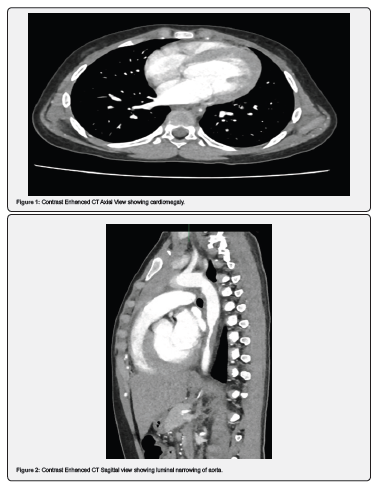

A 11-year-old girl reported to the ENT department of Federal Government Polyclinic Hospital, Islamabad, with complaints of intermittent headaches for one year and epigastric discomfort. Examination revealed elevated blood pressure with a systolic over diastolic value of 210/130mm Hg, and disproportionate blood pressure in bilateral upper and lower limbs. She was referred to the pediatric department, where preliminary tests showed a normal complete blood count but a lipid profile with elevated triglycerides (261mg/dL). Echocardiography performed by a pediatric cardiologist suggested severe abdominal coarctation (Figure 1-3).

She was then referred to the radiology department for a CT aortogram, which showed marked concentric narrowing of the descending thoracic aorta from the T6 to T9 vertebral bodies, with circumferential mural thickening at the T7 vertebra. The aorta returned to normal caliber distally to the T10-T11 level, with noted intimal thickening at the aortic hiatus along its lateral wall. There was also extension of intimal thickening into the abdominal aorta, its major branches, and bifurcation, though these branches were of normal caliber distally. Mild cardiomegaly with left-sided cardiac chamber enlargement was noted. Based on these findings, mid-aortic syndrome was suggested. The patient had experienced multiple episodes of headache and epigastric discomfort but had not been previously investigated or diagnosed. After proper investigations and diagnosis, the patient has been referred to the pediatrics vascular department for the treatment purpose (Figure 4).